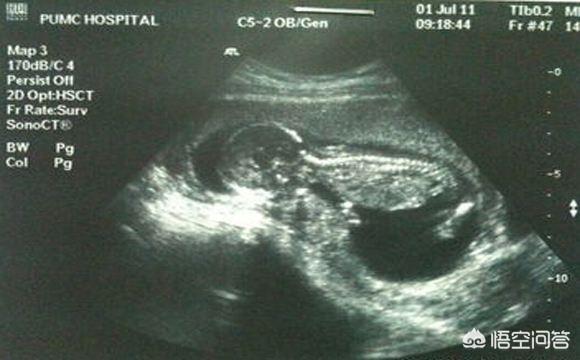

B超音波検査は一般的に胎児の発育と胎盤の位置をチェックするもので、胎児の病気の問題に関わることはほとんどありません。 4D超音波検査だけが胎児の奇形をスクリーニングするものなので、あなたが質問しているのはB超音波検査ではなく4D超音波検査のはずです。

4D超音波検査は、Bスキャン超音波検査の拡張版であり、胎児の奇形、胎児の顔や体の器官、四肢の奇形、例えば、胎児の口唇裂、合指症、四心室、内臓外反などを検出することができる。

妊娠中の4D超音波検査は、胎児の先天性心疾患、水頭症、口唇口蓋裂、四肢の発育をチェックすることができます。4D超音波検査では、母体内の胎児の動く画像も見ることができる。

超音波(4D超音波)は妊娠検査に必要なもので、主に胎児の体表や様々な臓器に奇形がないかをスクリーニングする役割を担っています。例えば、胎児の心臓、脳、腎臓、その他の部分の病気などです。

近年人気の超音波検査法である4D超音波検査を挙げる回答が多かった。 胎児の姿をより鮮明に見ることができ、母親や父親になる人に喜びや楽しみを与えるだけでなく、ビデオや写真を記録して記念に残すこともできる。